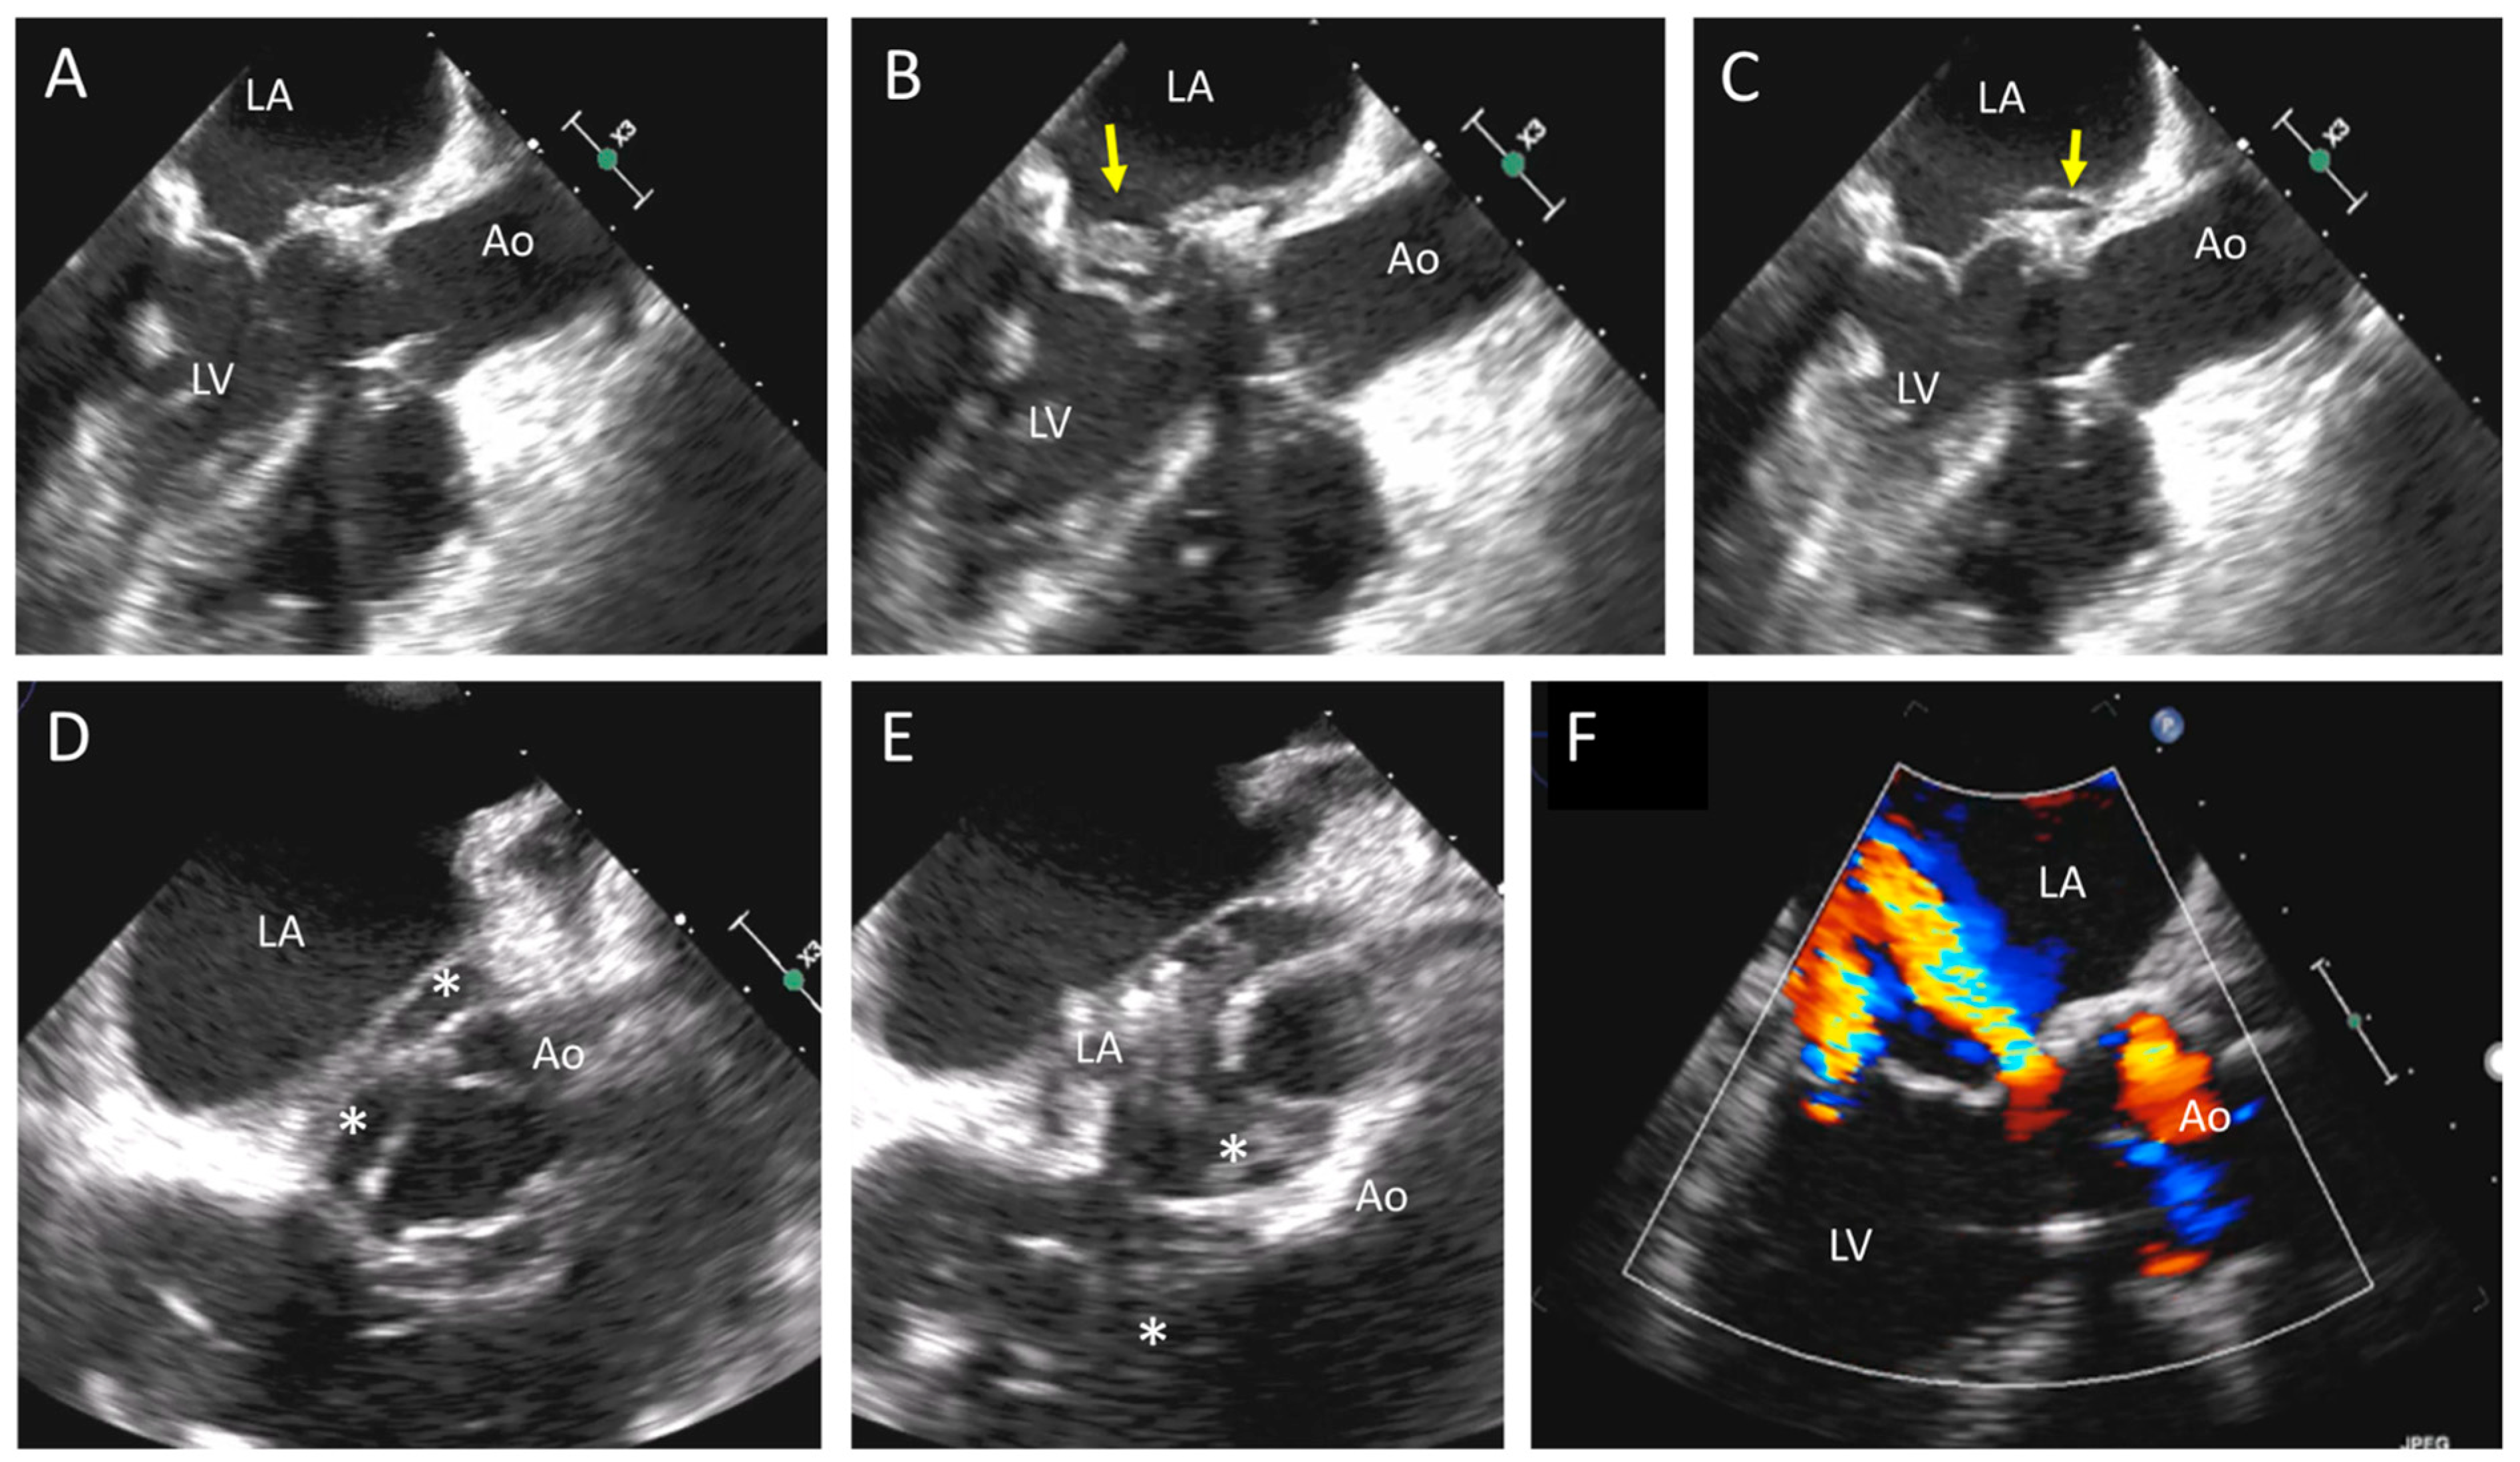

Figure 3. Biological aortic valve thrombosis. (A,B) Apical long axis and apical 5-chamber adapted views showing thrombosis of the prosthesis (arrows). (C) Marked increase of the Doppler systolic aortic gradient. (D) Anatomical appearance of the prosthesis (surgical specimen), the arrows indicate the presence of thrombosis of leaflets’ surface. (E) 3D TEE imaging of the valve. LA, left atrium; LV, left ventricle; TEE, transesophageal echocardiography.

Figure 5. Transesophageal echocardiography of complex endocarditis in a patient with biological mitral and aortic prosthesis. (A,B) From a mid-esophageal view, there is a normal leaflet appearance (A), and in a systolic frame, there is the presence of vegetation (B, arrow). (C) The arrow indicates an aortic pseudoaneurysm in the mitral–aortic intervalvular region. (D,E) Short axes of the aortic valve (upper-esophageal view) showing a large abscess of the periaortic tissue (asterisks). (F) Color-Doppler also shows a LVOT/left atrial fistula located at the base of the mitral valve. Ao, aorta; LA, left atrium; LV, left ventricle; LVOT, left ventricle outflow tract.